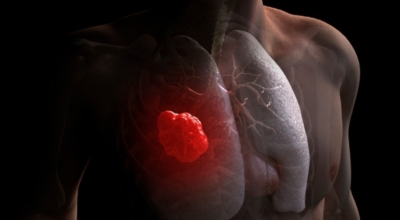

폐에 발생된 악성 종양을 말하며 오랜 기간 흡연해온 남성들에서 발병률이 높고 최근 들어 가지가지 환경적인 요인의 영향과 간접흡연으로 흡연하지 않는 여성에서도 많이 발생하고 있어요. 증상을 느껴 병원을 찾았을 때는 수술하기 늦은 경우가 많아 사망하는 비율이 매우 높은 암입니다. 폐 자체에서 생기거나 다른 장기에서 발생된 암이 폐로 전이되어 나타나기도 하고 특별한 초기 증상이 없는 경우가 많다고 하며 암이 진행된 후에도 일반적인 감기 증상인 기침과 가래 외의 특이 증상이 나타나지않아 증상만으로는 진단이 쉽지 않아요.

폐암 역시 다른 암들과 마찬가지로 조기 발견 및 치료가 매우 중요하므로 일상 속에서 폐암 초기증상을 간과하지 않도록 주의를 기울여야 해요. 따라서 긴 시간의 흡연, 간접흡연에 노출됐거나 평상시 폐 기능이 좋지 않고 호흡기 질환에 잘 걸리는 예민한 편이라면 폐암 초기증상에 관하여 잘 알아뒀다가 이상이 있다고 생각되면 최대한 빨리 전문의를 찾아 정확한 검진을 받아보는 편이 좋아요.